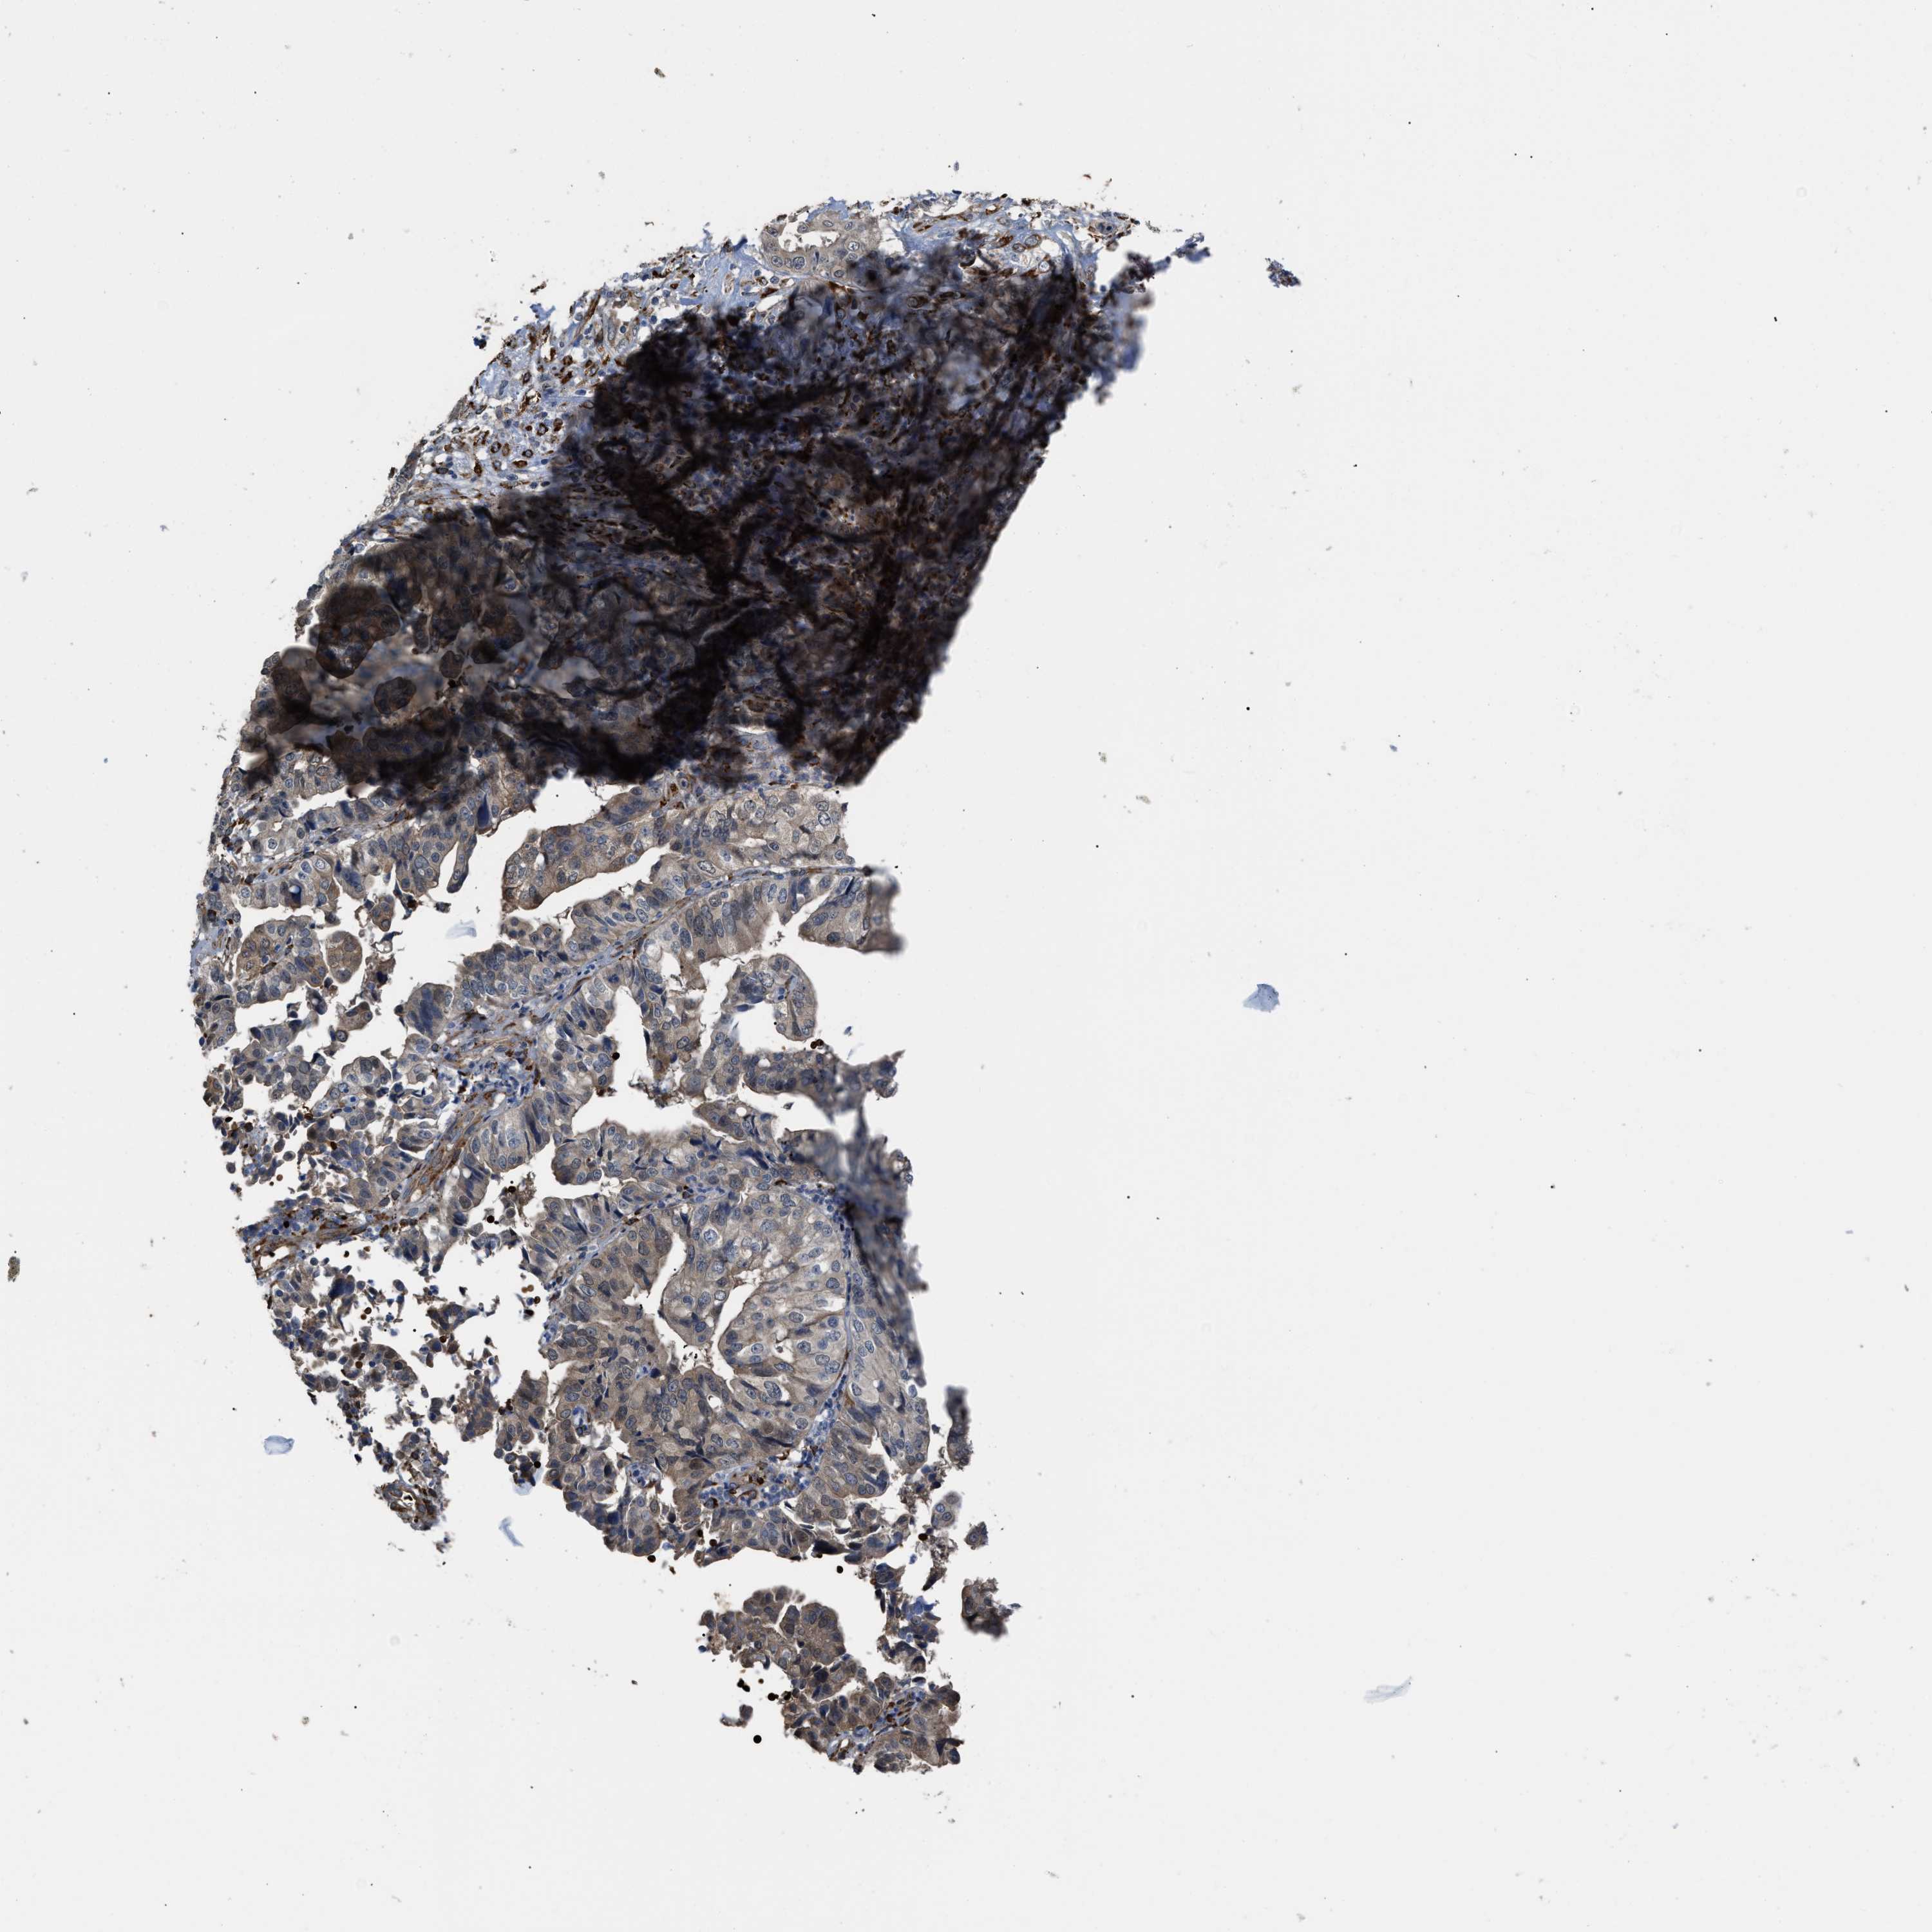

LIVER CANCER - Protein expressioni

A mouse-over function shows sample information and annotation data. Click on an image to view it in a full screen mode. Samples can be filtered based on level of antibody staining by selecting one or several of the following categories: high, medium, low and not detected. The assay and annotation is described here.

Note that samples used for immunohistochemistry by the Human Protein Atlas do not correspond to samples in the TCGA dataset.

Antibody stainingi

Antibody staining in the annotated cell types in the current human tissue is reported as not detected, low, medium, or high, based on conventional immunohistochemistry profiling in selected tissues. This score is based on the combination of the staining intensity and fraction of stained cells.

Each image is clickable and will lead to virtual microscopy that enables deeper exploration of all samples and also displays staining intensity scores, fraction scores and subcellular localization as well as patient and tissue information for each sample.

Antibody HPA019601

Antibody CAB008667

Staining

High

Medium

Low

Not detected

Intensity

Strong

Moderate

Weak

Negative

Quantity

>75%

75%-25%

<25%

None

Location

Nuclear

Cytoplasmic/membranous

Cytoplasmic/membranous,nuclear

Carcinoma, Hepatocellular, NOS

Cholangiocarcinoma